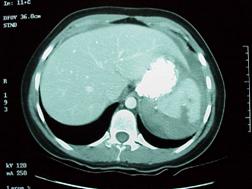

Leziune hepatica intraparenchimatoasa Leziune de lob drept

hepatic

Leziune de splina Leziune de splina

Traumatism abdominal inchis

Leziune de pancreas ( ambele foto)